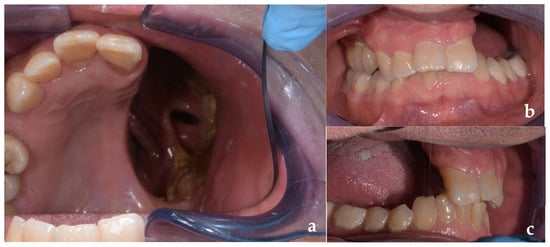

Surgical Procedures to Enhance Prosthetic Prognosis in the Rehabilitation of a Maxillectomy Defect Due to Sinonasal Carcinoma: A Case Report

by Armando Crupi, Giancarlo Pecorari, Vincenzo Ronsivalle and Marco Cicciù

Background: Rehabilitation of head and neck cancer patients with acquired intraoral defects is challenging and requires multidisciplinary collaboration. This case report describes an integrated surgical and prosthetic approach in which palatal obturator rehabilitation is used to restore palatal integrity, speech, swallowing, aesthetics, and overall quality of life after maxillectomy. The objective is to show how careful surgical planning to optimize prosthetic prognosis, combined with a precisely designed obturator prosthesis, can achieve satisfactory functional rehabilitation. Methods: A man in his 50s with sinonasal carcinoma underwent partial left maxillectomy followed by radiotherapy and chemotherapy. The defect was classified as Aramany class I and Brown class 2b, and the surgical resection was planned to preserve structures favorable to prosthetic support. Prosthetic management included fabrication of a removable partial denture incorporating a hollow-bulb obturator. Results: During trial and delivery, the patient demonstrated improved speech and swallowing, enhanced denture stability, and favorable aesthetics. The patient reported satisfaction with functional and cosmetic outcomes and was provided with instructions for use and cleaning, with a plan for regular follow-up. Conclusions: Palatal obturator prostheses remain a gold standard for unilateral maxillectomy rehabilitation when adequate retention is achievable. Surgical-prosthetic collaboration permits restoring palatal contours, and dentition can normalize speech and swallowing, and substantially improve the quality of life. Full article